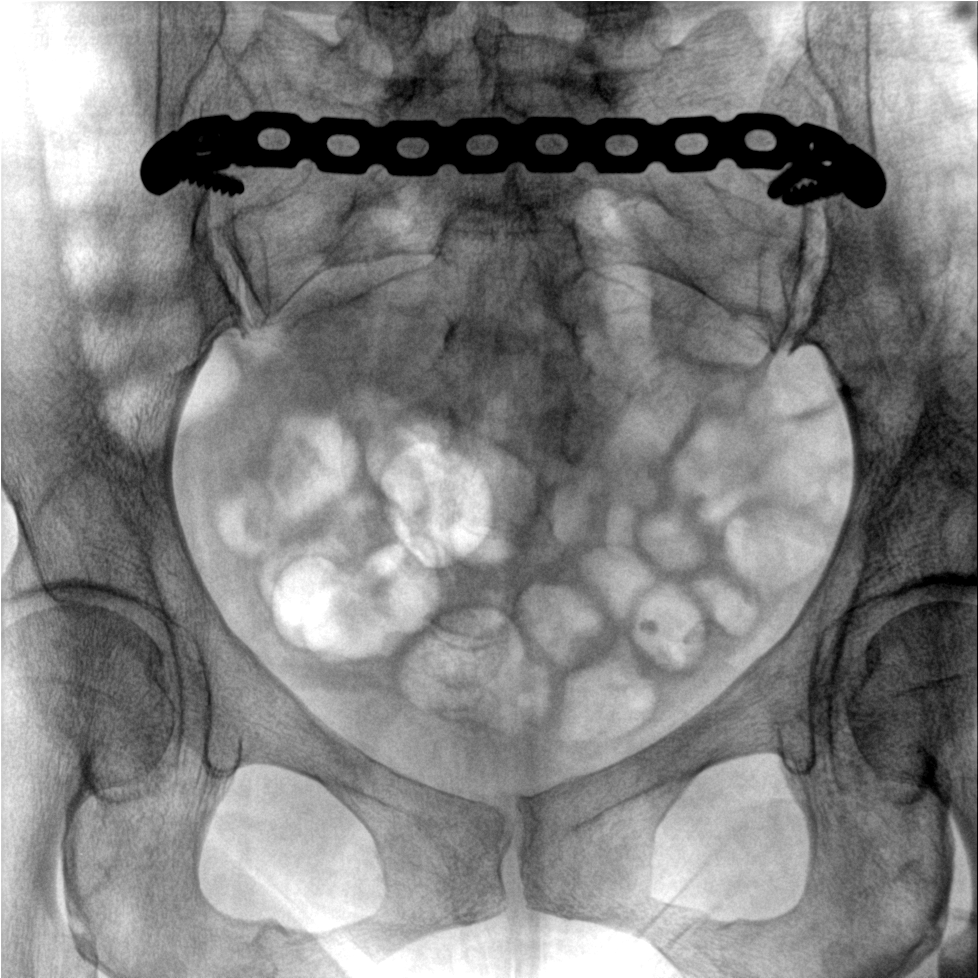

提供更大的術中三維成像視野,采集更多圖像信息,可一次拍全全段頸椎、全段腰椎、七節胸椎、雙側骶髂關節、股骨頭及單側盆骨。